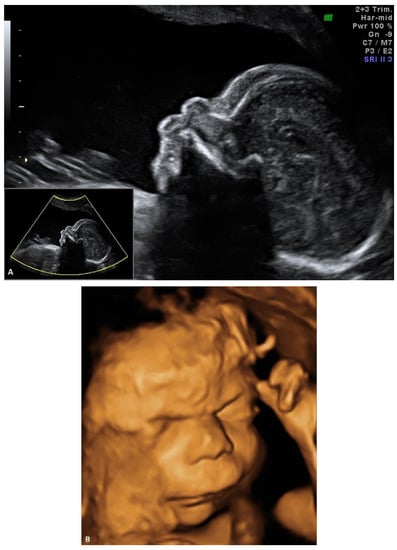

4. Prenatal Presentation of a Classical CDLS Case

We report a case of prenatal diagnosis of CDLS at 29 weeks’ gestation in a 30-year-old woman who had previously delivered a normal baby. The patient was referred to our fetal medicine unit because of fetal growth restriction, diagnosed at 24 weeks’ gestation. As no Doppler flow anomalies were detected, a genetic anomaly (lethal trisomy) rather than placental insufficiency was suspected by the referring doctors. Ultrasound examination in our unit demonstrated symmetrical fetal growth restriction with normal Doppler studies. The amniotic fluid was increased with a deepest vertical pool of 9.2 cm. Examination of the fetal face showed abnormal profile, synophrys, depressed nasal bridge, long downturned upper lip, and micrognathia (Figure 1A,B). Cardiac examination demonstrated abnormal flow through the atrio-ventricular, aortic, and pulmonary valves. The third finger of the right fetal hand was missing, and the fingers of the left hand were overlapping.

Figure 1.

Ultrasound examination of the fetal face in a CDLS case with classical phenotype: (A) 2D image of the fetal profile at 29 w of gestation, showing mild micrognathia/retrognathia; abnormal philtrum; depressed nasal bridge; (B) Volume reconstruction of the fetal face at 29 w of gestation; (C) Volume reconstruction of the fetal face at 34 w of gestation.

The initial ultrasound findings persisted in the third trimester (Figure 1C). As pregnancy progressed the polyhidramnios worsened but did not become tense and did not require amniodrainage. Fetal skin edema was seen in late pregnancy.